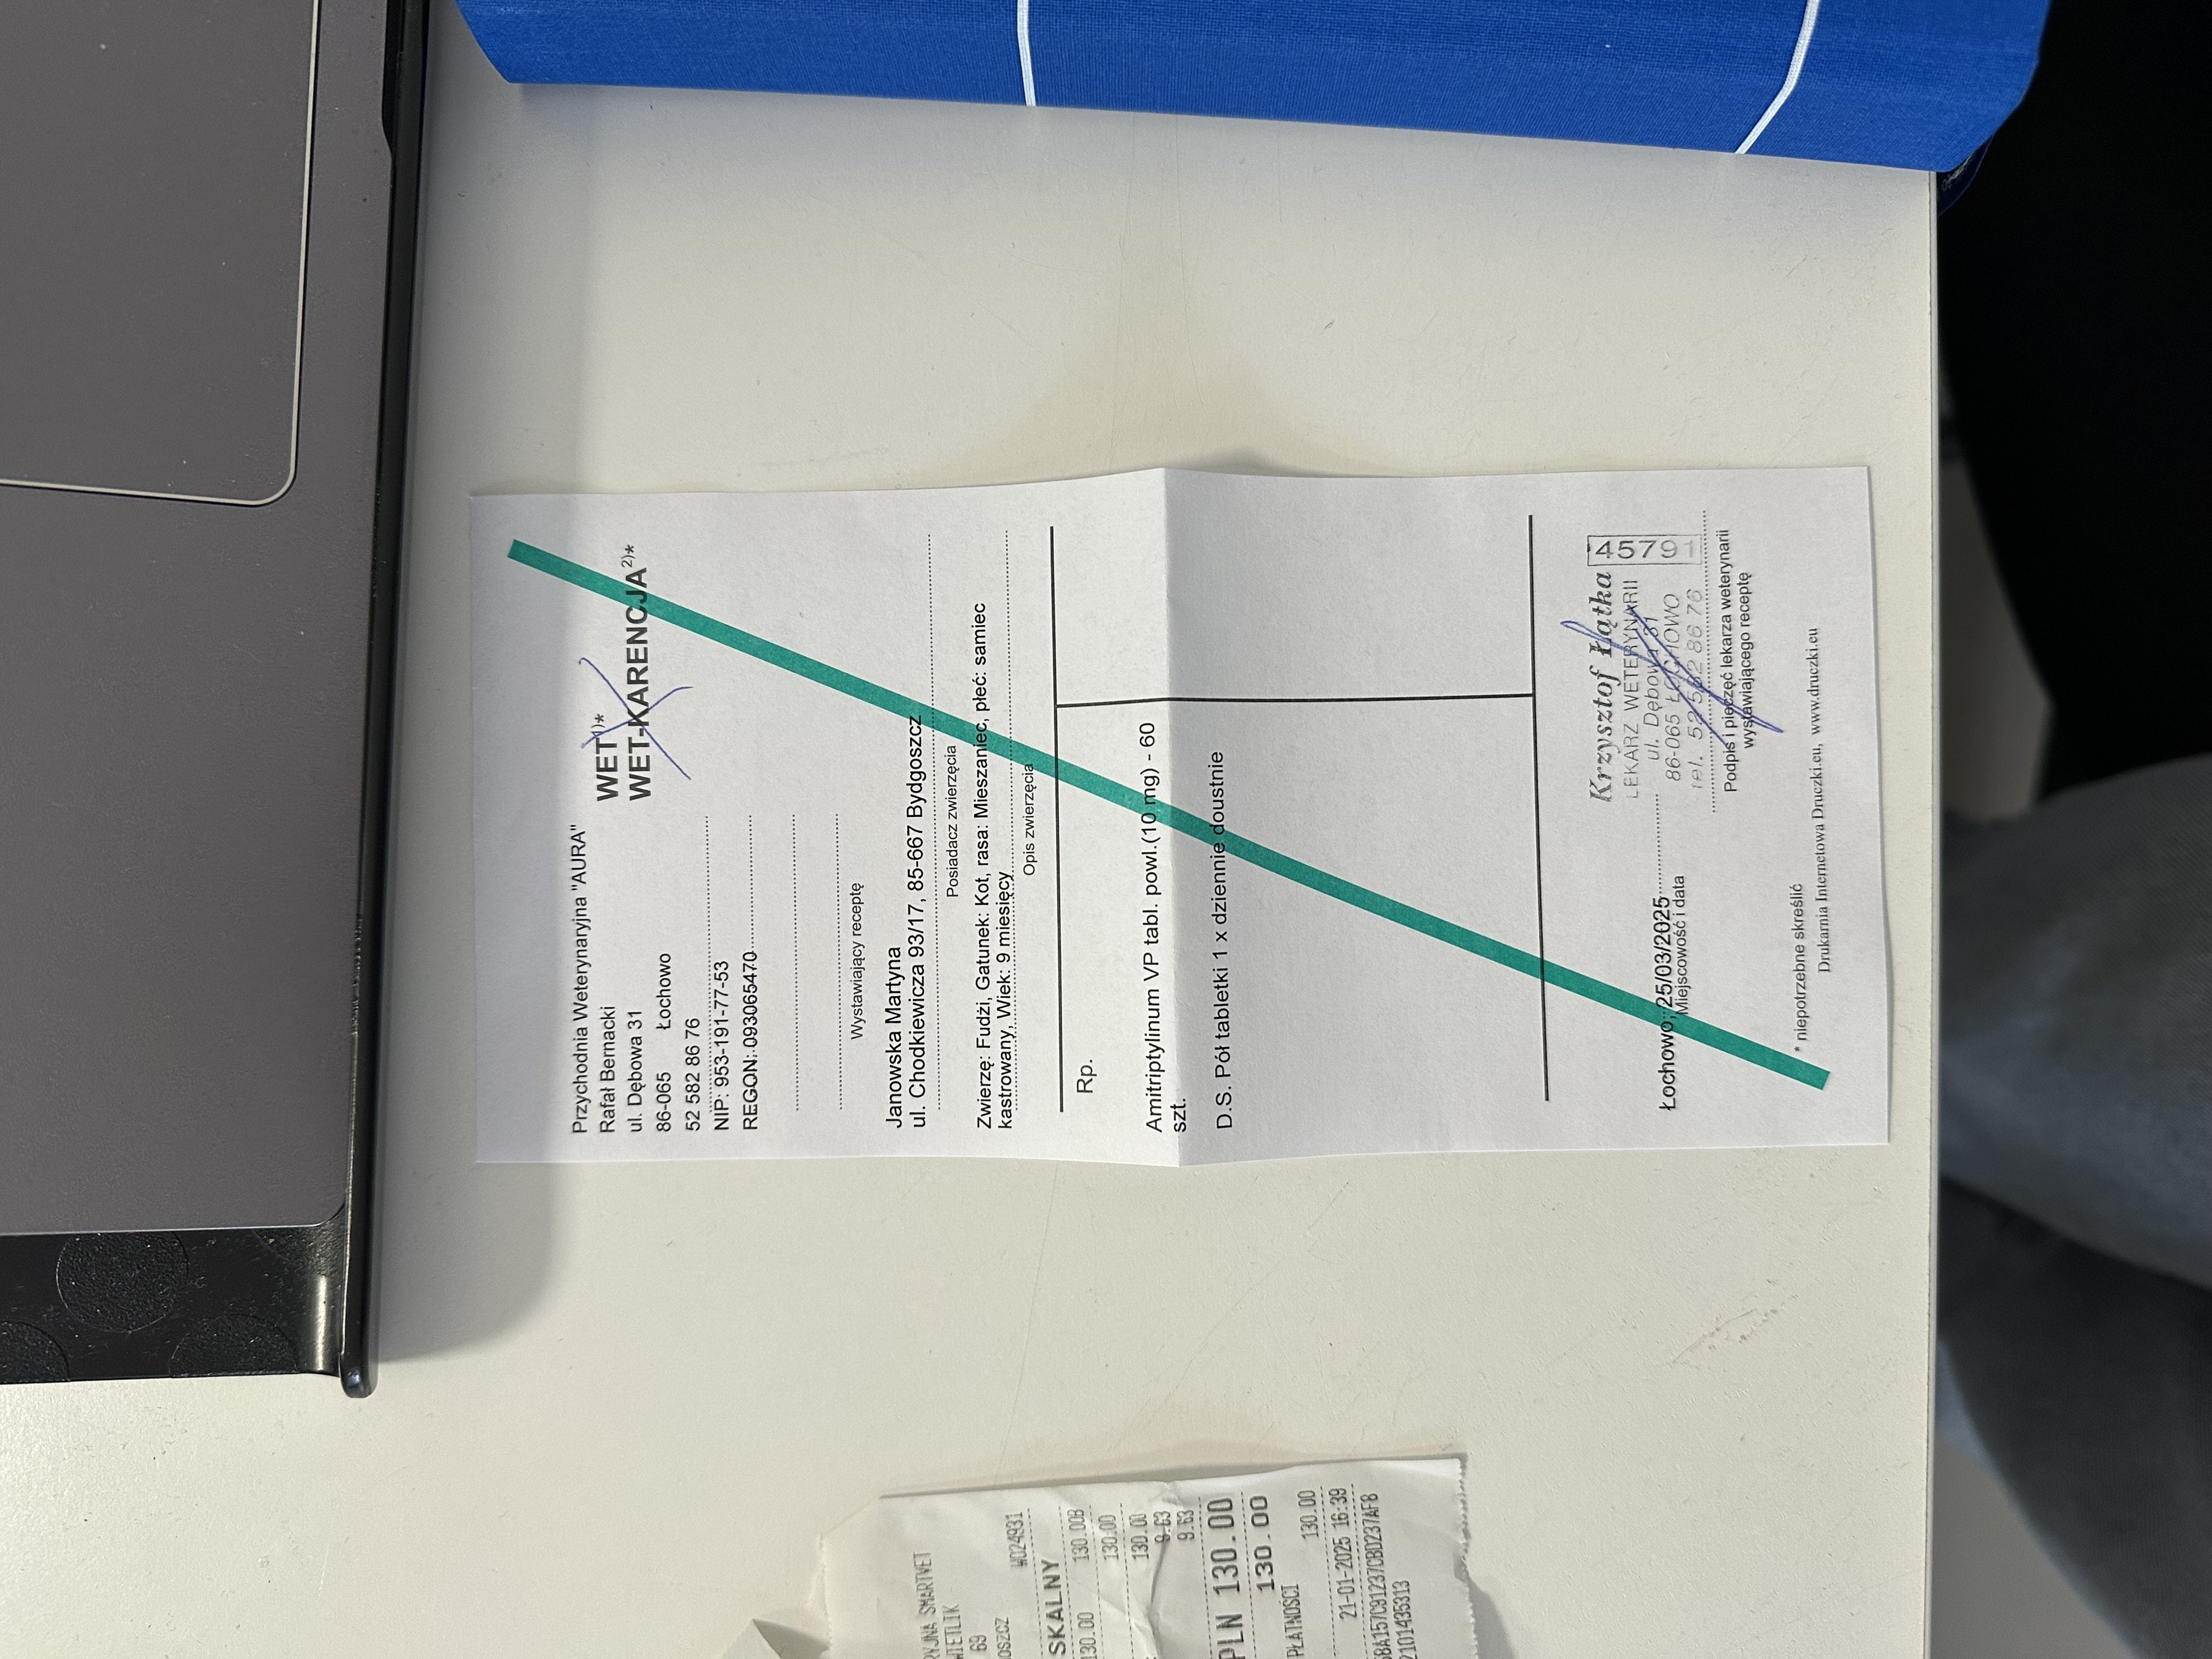

Lekarz wprowadził leczenie objawowe, aby sprawdzić, czy Fudżi dobrze na nie zareaguje: Amitryptylina – lek przeciwdepresyjny i przeciwbólowy, stosowany przy zaburzeniach Pnrednicorton (steryd) – silny lek przeciwzapalny, mający zmniejszyć stan zapalny i świąd.